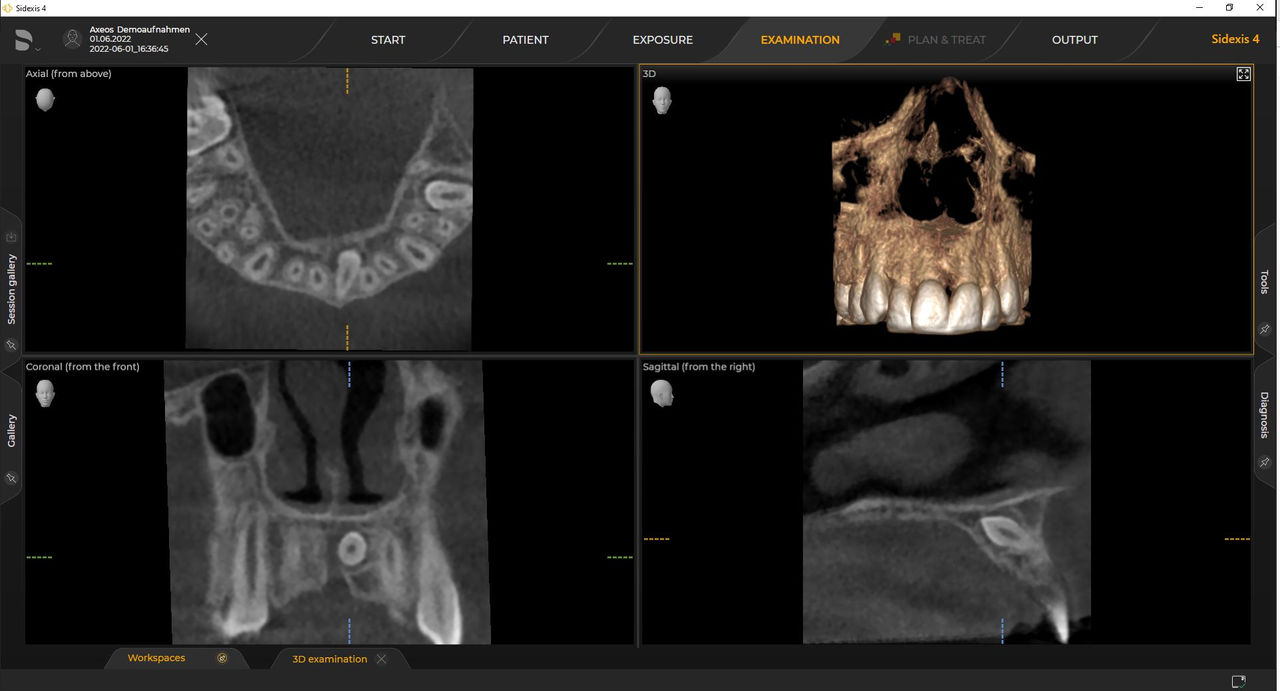

Las unidades 3D de Dentsply Sirona funcionan exclusivamente con Sidexis 4. Sin embargo, la migración de datos de Sidexis XG a Sidexis 4 es muy fácil. Sidexis 4 permite una experiencia digital completa con las últimas herramientas.